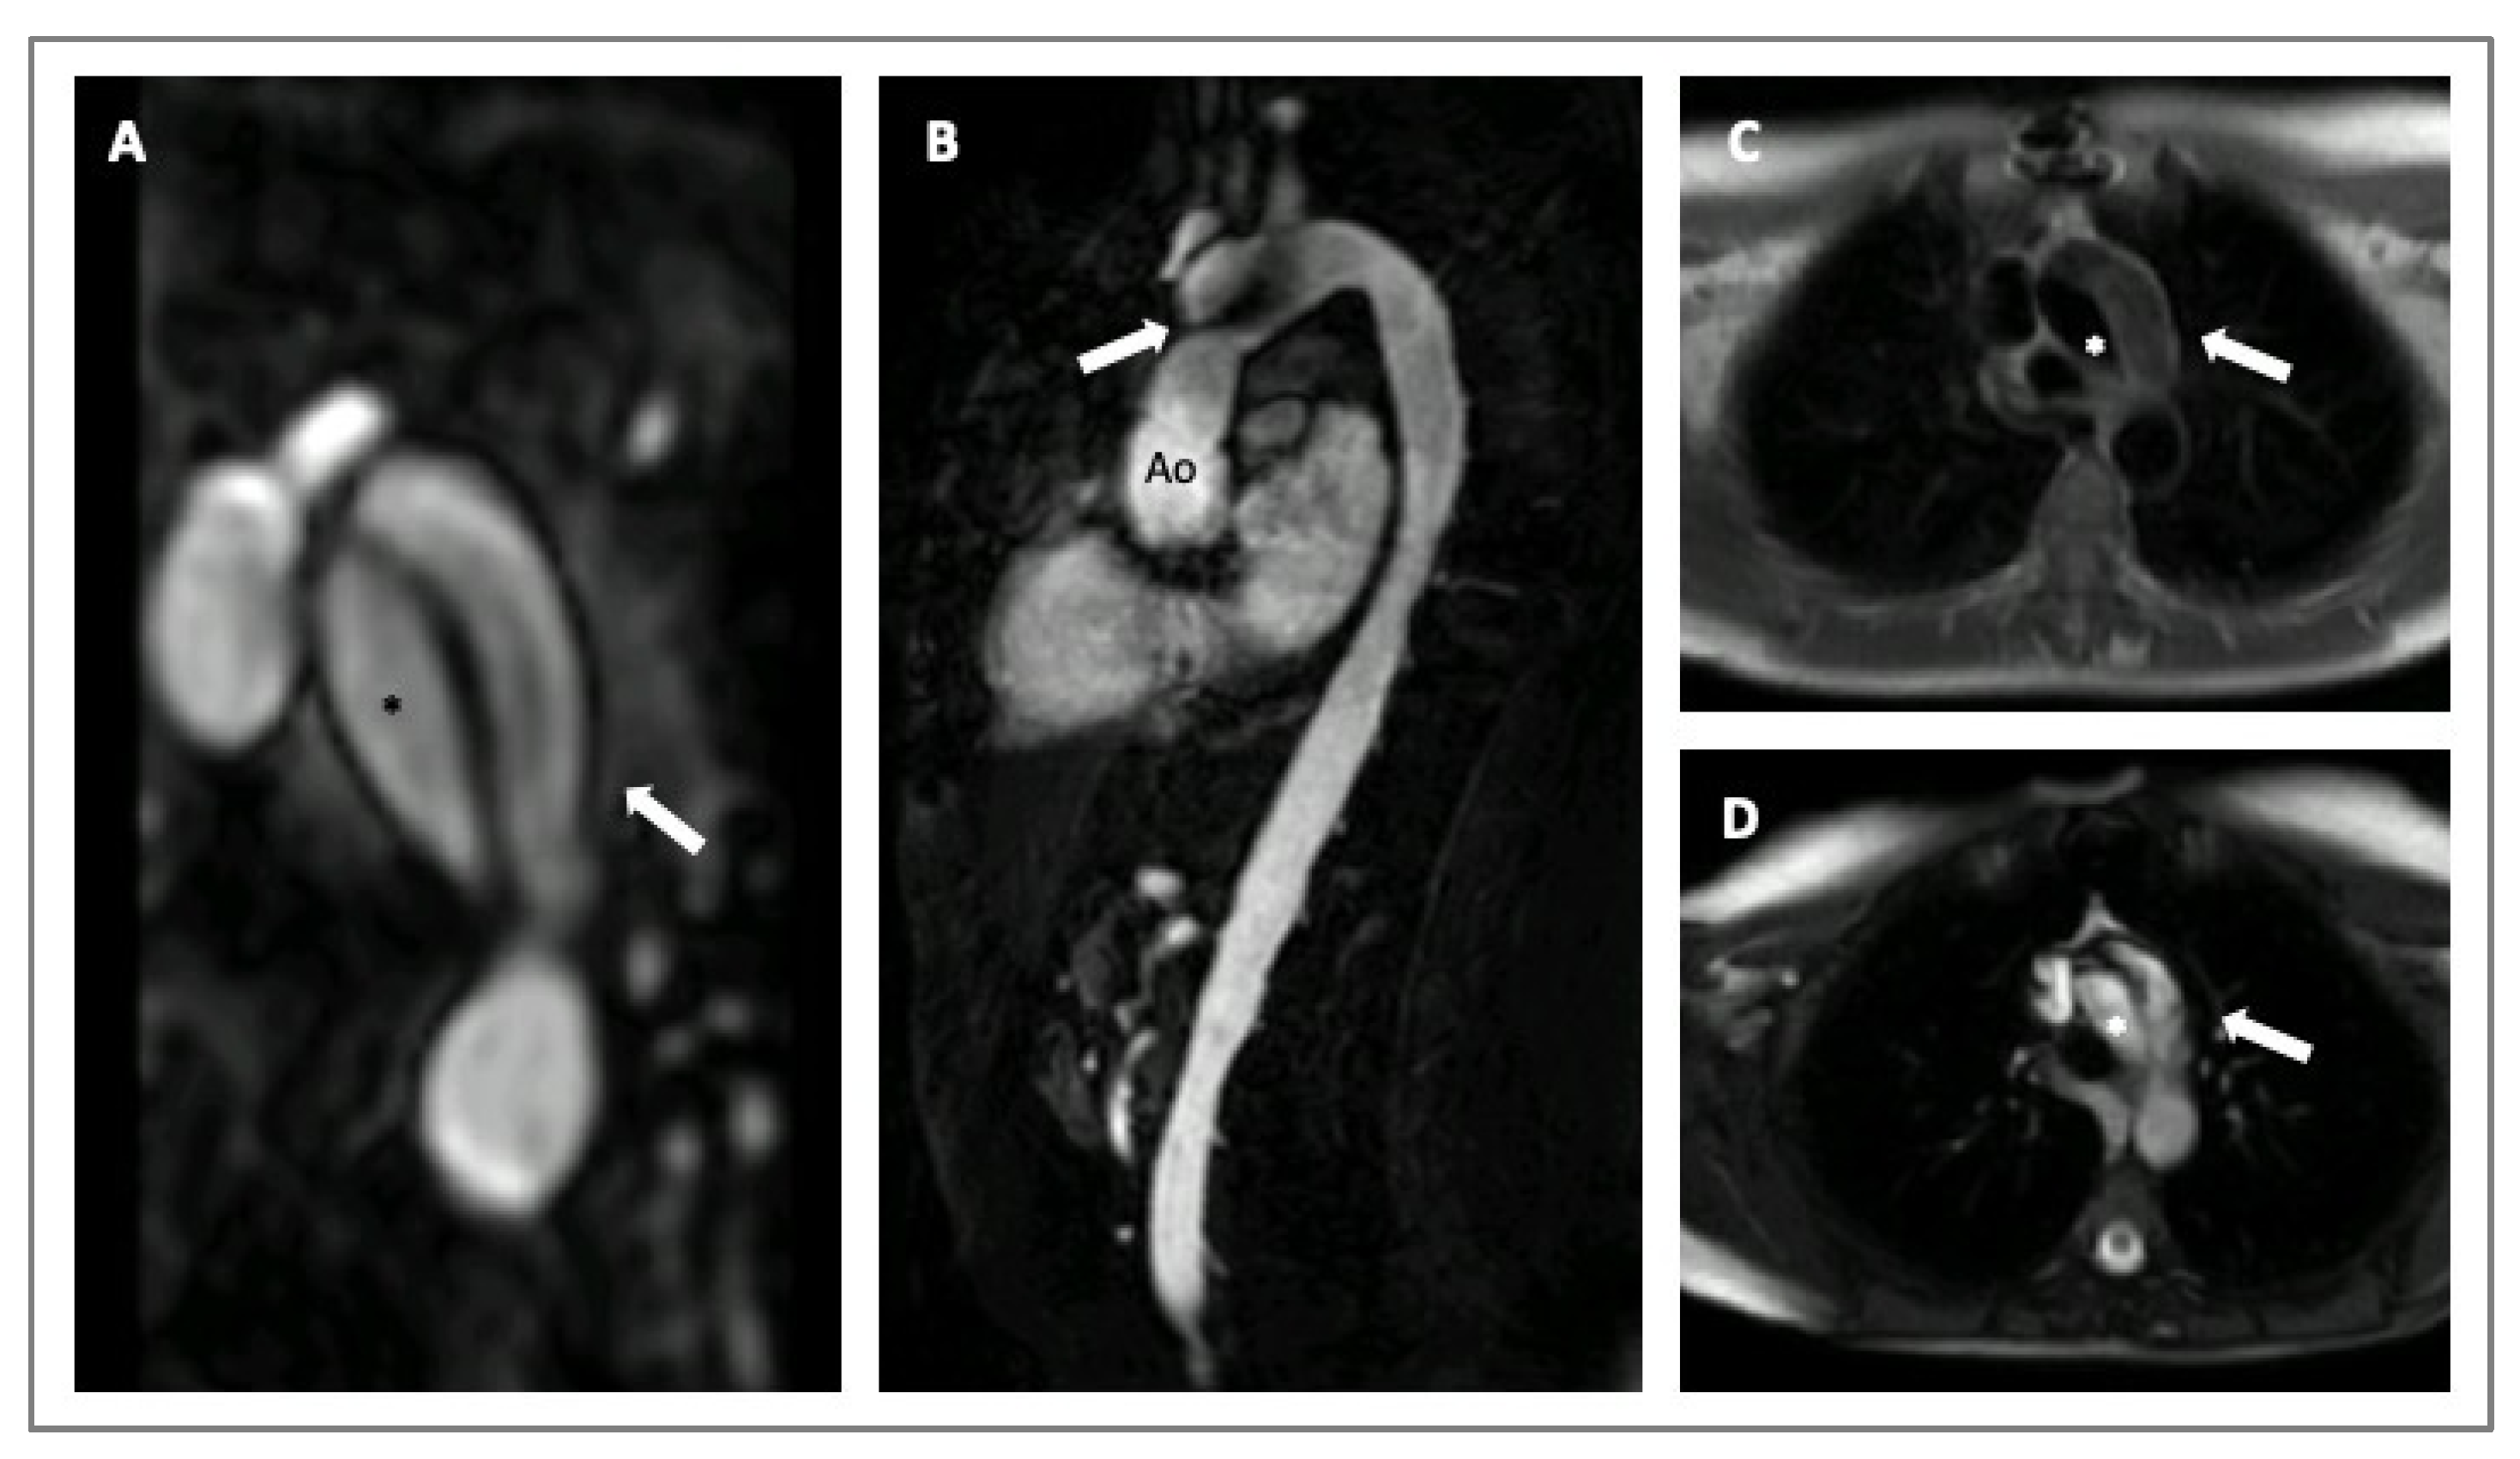

4. Imaging in HTADs

- Lenz, A.; Warncke, M.; Wright, F.; Weinrich, J.M.; Schoennagel, B.P.; Henes, F.O.; Adam, G.; von Kodolitsch, Y.; Schoen, G.; Bannas, P. Longitudinal follow-up by MR angiography reveals progressive dilatation of the distal aorta after aortic root replacement in Marfan syndrome. Eur. Radiol. 2023, 33, 6984–6992. [Google Scholar] [CrossRef]

- Evangelista, A.; Sitges, M.; Jondeau, G.; Nijveldt, R.; Pepi, M.; Cuellar, H.; Pontone, G.; Bossone, E.; Groenink, M.; Dweck, M.R.; et al. Multimodality imaging in thoracic aortic diseases: A clinical consensus statement from the European Association of Cardiovascular Imaging and the European Society of Cardiology working group on aorta and peripheral vascular diseases. Eur. Heart J. Cardiovasc. Imaging 2023, 24, e65–e85. [Google Scholar] [CrossRef] [PubMed]